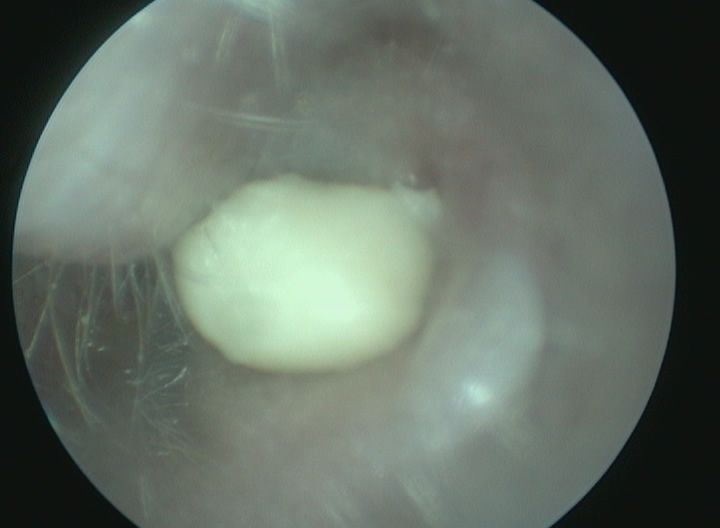

Pour prévenir cette maladie, seule la consommation de foin (foin de Crau ou de phléoles) ou d'herbe fraîche permet l'usure efficace des molaires. Les signes de malocclusion sont des signes de salivation, de refus de s'alimenter, de l'amaigrissement et l'apparition de sécrétions oculaires. En cas d'infection, on observera l'apparition d'abcès dentaires. Le traitement fait appel à la taille des dents sous anesthésie (appelée parage dentaire) par un vétérinaire spécialisé. Cette taille de dent est, si possible, réalisée à l'aide d'une caméra endoscopique pour examiner les dents localisées dans le fond de la cavité buccale et évaluer des lésions plus discrètes.

On distingue les otites externes qui affectent le pavillon auriculaire externe, les otites moyennes qui concernent la partie osseuse de l'oreille (bulle tympanique) et qui se situe sous le tympan (donc non visible extérieurement) et les otites internes (organe de l'équilibre). L'observation se fait préférentiellement par endoscopie ou otoscopie. Le diagnostic d'otite moyenne se fait à l'aide d'un scanner ou un IRM préférentiellement. En fonction de l'atteinte considérée, plusieurs techniques chirurgicales peuvent être recommandées pour permettre la vidange des bulles tympaniques (bullotomie ventrale, PECALBO ou chirurgie d'abaissement du conduit auriculaire). Des techniques endoscopiques sont également possible pour aborder la bulle tympanique (myringotomie).